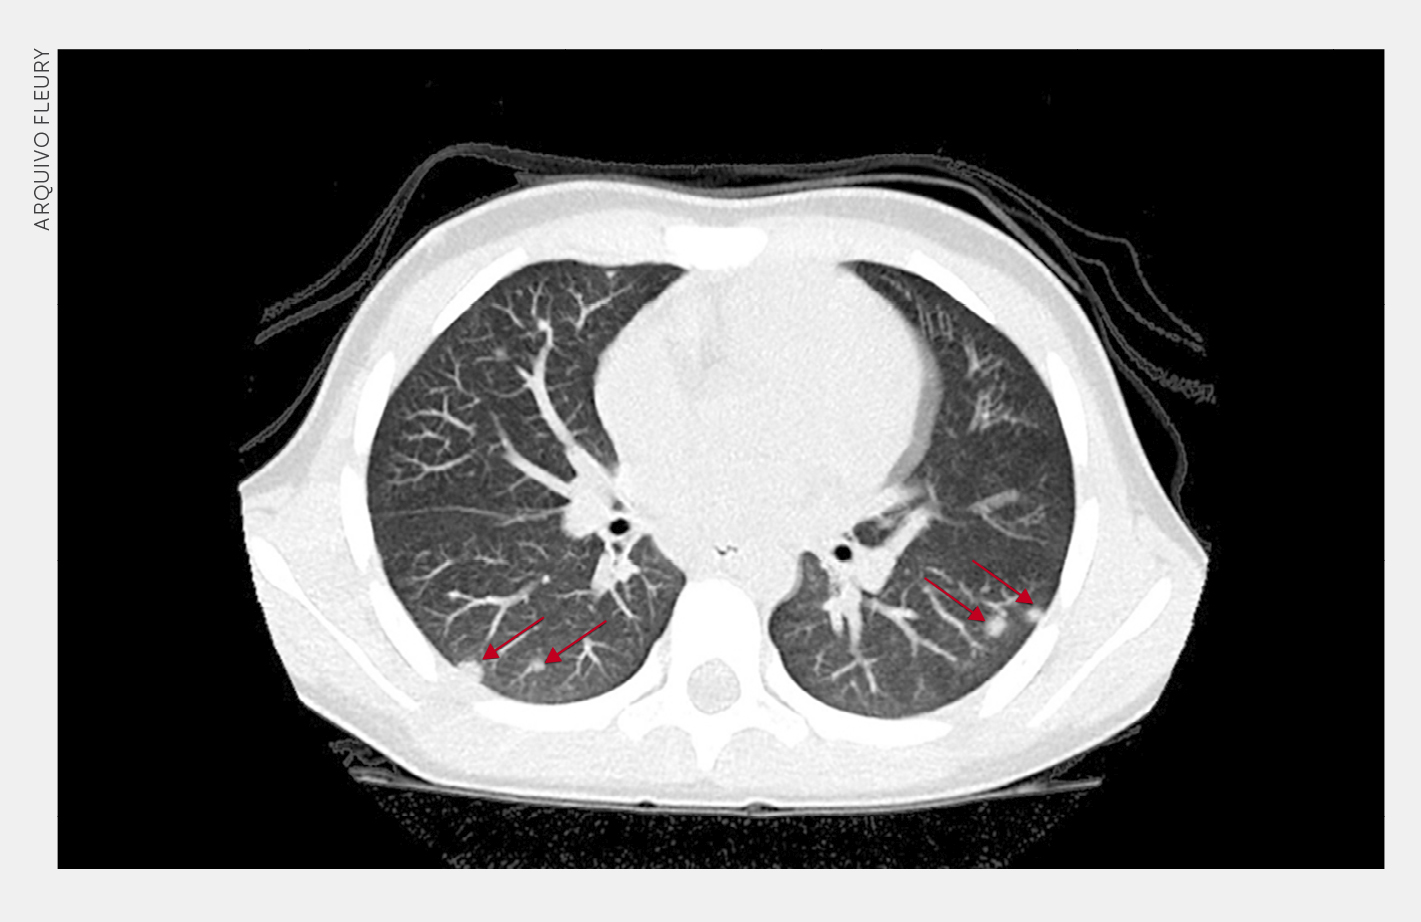

TC de tórax mostra múltiplos pequenos focos de consolidação com halo em vidro fosco (setas), de distribuição randômica, alguns subpleurais. No laudo, o radiologista classificou a imagem como indeterminada para pneumonia viral por Covid-19, admitindo diagnóstico diferencial com outras pneumonias (virais e não virais) ou processos não infecciosos.

Embora as alterações tomográficas, na Covid-19, não sejam patognomônicas na população pediátrica, um padrão de opacidades em vidro fosco ou de focos de consolidações periféricas e/ou subpleurais, geralmente bilaterais, predominando nos lobos inferiores, sugere o diagnóstico em um contexto clínico apropriado. O sinal do halo, que descreve uma consolidação focal com opacidade em vidro fosco ao redor, foi relatado em até 50% dos casos pediátricos e, portanto, ajuda a restringir o diagnóstico diferencial quando presente.